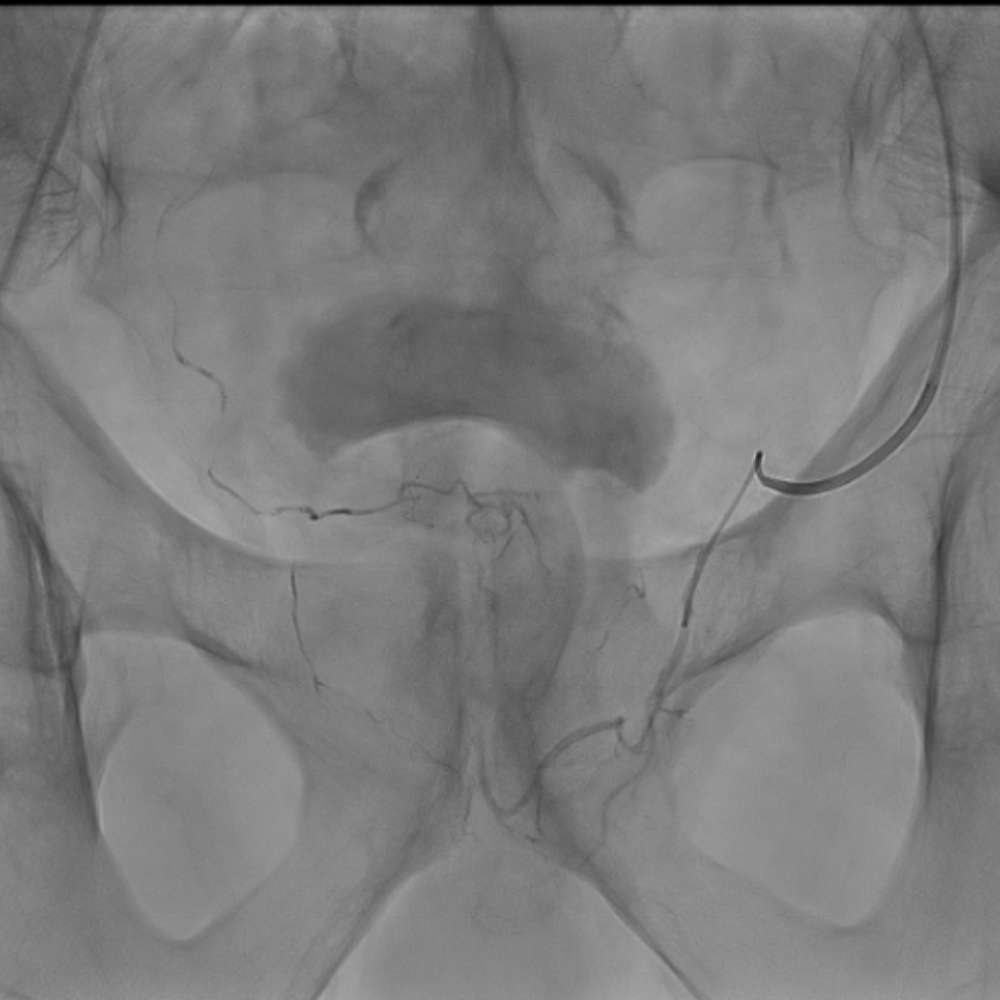

תמונות מהצנתור:

- לפני החסימה: נראית זרימה עשירה לעורקי הערמונית המוגדלת, הצנתר נמצא בצד שמאל ובעת הזרקת חומר הניגוד ישנם עורקים משותפים לשמאל וימין. כאשר מזריקים את חומר הניגוד מצד שמאל, צד ימין מתמלא באופן מלא. המצב יכול לרמז על היצרות או חסימה במוצא עורק הערמונית הימני.

- ממשיכים כעת לצד ימין וניתן לראות שהעורקים נצבעים בהיקף הערמונית בלבד מכיוון שהרקמה נחסמה כבר מקודם דרך הצד השני.